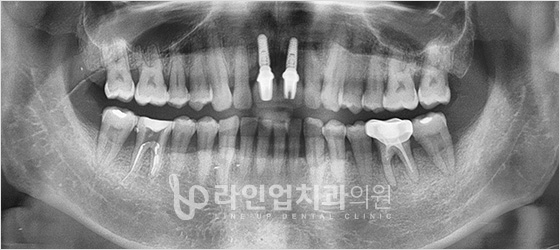

Before

After

Incisive teeth implant